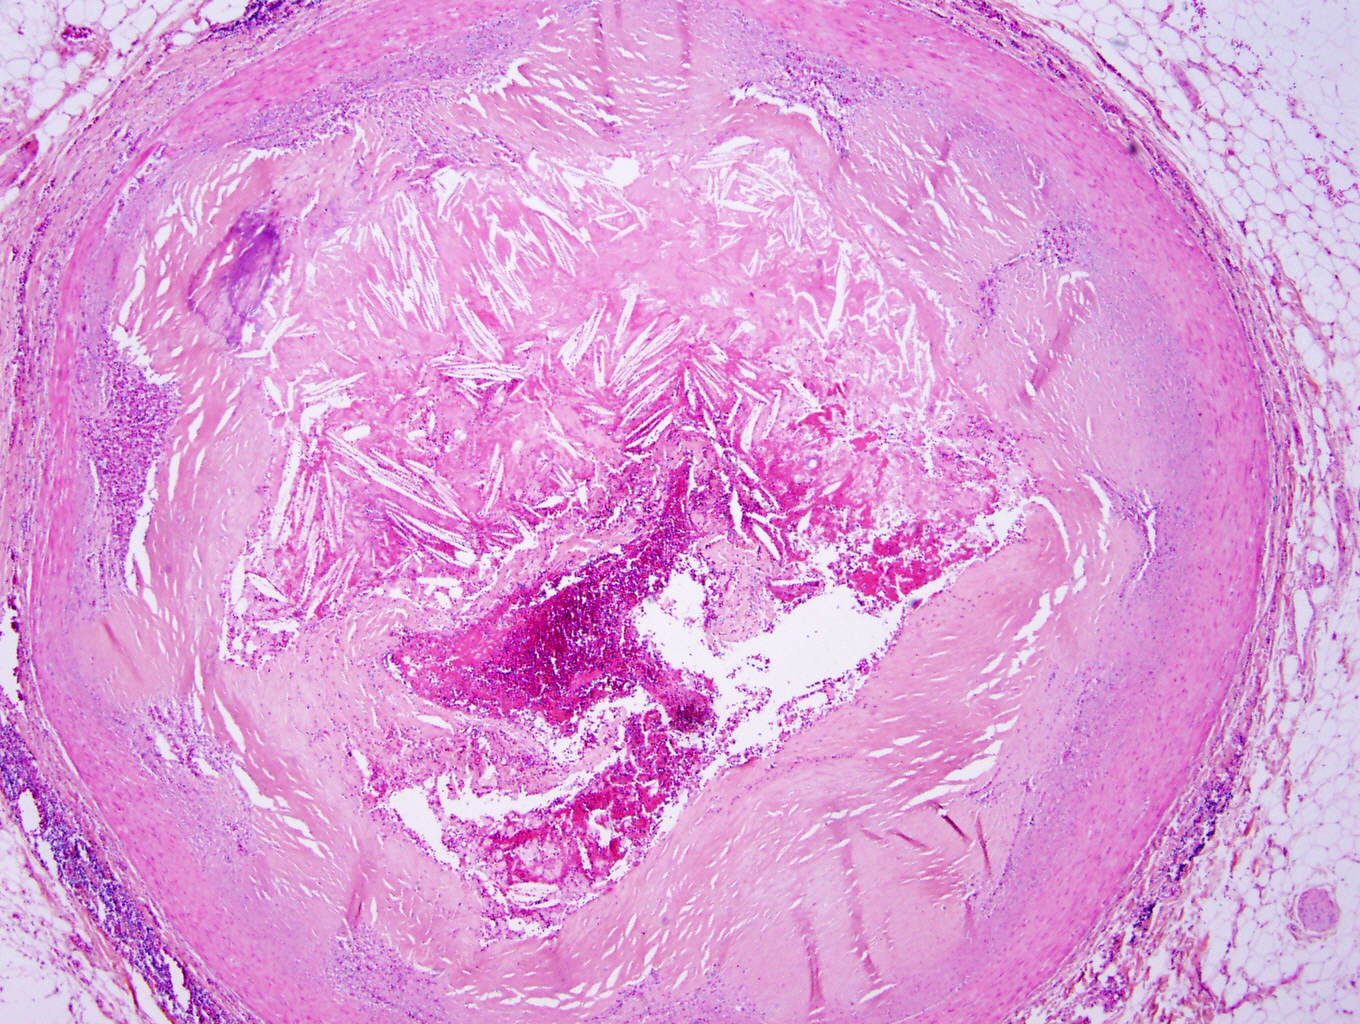

Microscopic (histologic) description

- Fatty streak: subendothelial accumulation of foam cells without necrotic core or fibrous cap

- Fibrous cap atheroma (Am J Med 2009;122:S3):

- Well formed necrotic core with overlying fibrous cap; smooth muscle cells, macrophages, lymphocytes and connective tissue components may be present

- With rupture: luminal thrombus communicates with underlying necrotic core

- With erosion: luminal thrombosis; no communication of thrombosis with necrotic core

- Fibrocalcific plaque: collagen rich plaque, contains large areas of calcification with few inflammatory cells, necrotic core may be present

Microscopic (histologic) images